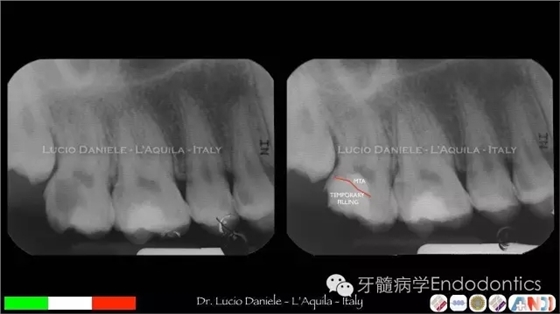

圖6.